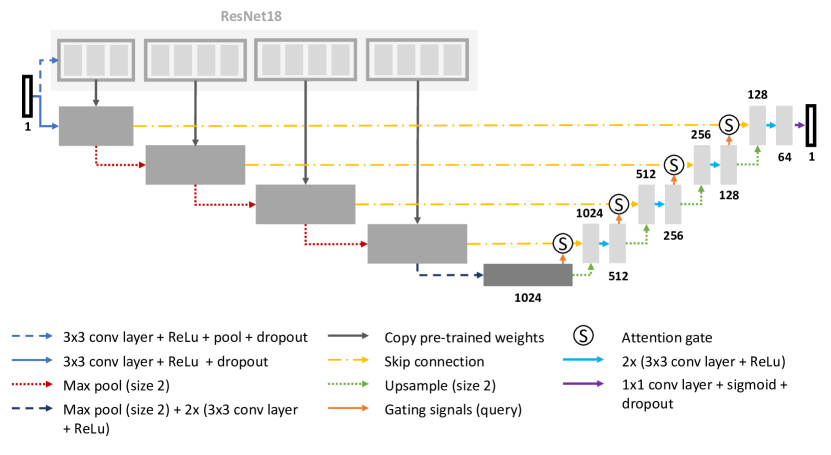

2.2.1 Proposed Architecture

The architecture of AURA-net consists of a deeper Attention U-net model, in which we replace the downsampling path with a ResNet-18 model pre-trained on ImageNet. The model is depicted in Figure 1. First, the pre-trained ResNet accelerates learning when few annotations are available during training. Second, Attention mechanisms help the network focus on relevant features in poorly contrasted images. Finally, the AC loss captures region information, making up for the faint or absent edges. As a result, our model, combining these strategies in a U-Net architecture, is perfectly suited to the segmentation of PC microscopy datasets when only a small set of annotations is available.